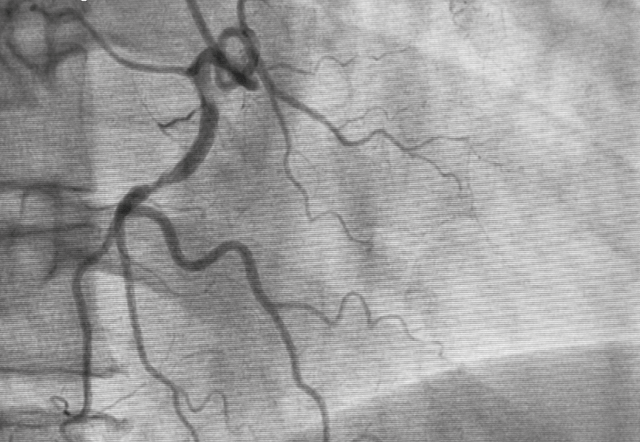

Foram incluídos 610 pacientes, 305 randomizados a TRA e 305 a TFA. A idade média foi de 61 anos. A maioria dos pacientes eram homens. O vaso tratado mais frequentemente foi a artéria coronária direita, seguida da artéria descendente anterior.

No que se refere aos resultados, o TRA foi não inferior ao acesso femoral no sucesso do procedimento. Por outro lado, o acesso radial apresentou menos taxa de complicações relacionadas com o acesso (2,0% vs. 5,6%; p = 0,019). Finalmente, não houve diferenças na duração do procedimento, no volume de contraste utilizado ou na dose de radiação entre os dois grupos.